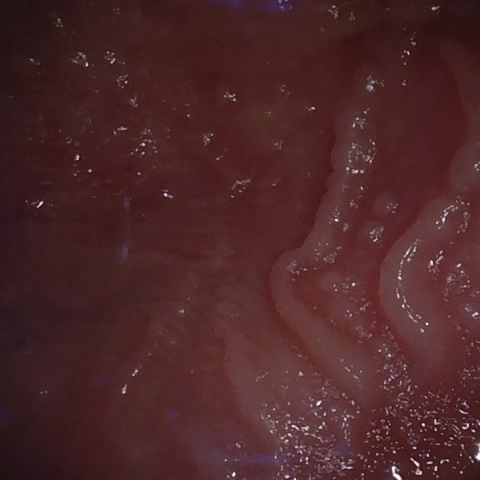

NHD39174

Annotated as "Good"

Original Image Rendering Image